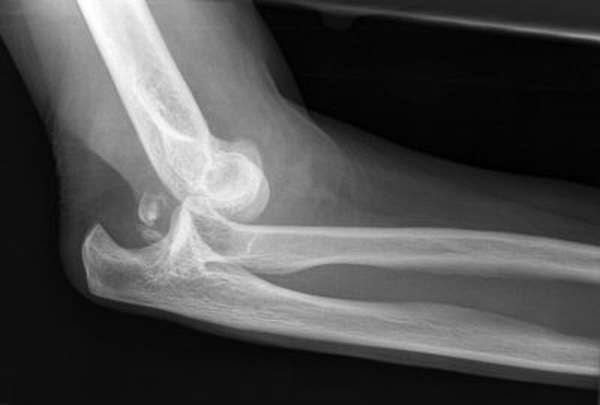

Для окончательного подтверждения диагноза потребуется рентген. Он особенно важен для установления возможных переломов. Рекомендуется делать снимок в двух или трех проекциях. Еще более точные данные дают современные технологии: компьютерная томография, магнитно-резонансная томография.

Перилунарный или же дорсальный

Этот вид вывиха возникает при падении на вытянутую руку на ладонь, при этом она находится в тыльном сгибании. После падения соотношение полулунной кости и лучевой не меняется, а все остальные структуры вместе с рукой претерпевают смещение вверх. Иногда многие специалисты объясняют это повреждением связочного аппарата.

Признаки данного вывиха сводятся к болезненности. Травматолог при физикальном обследовании замечает такие симптомы:

- Разлитая припухлость;

- Штыкообразная деформация;

- Пальцы полусогнуты.

При пальпации определяется локальная болезненность больше к тылу, где можно пропальпировать сместившиеся кости. Движения в суставе резко ограничены, при попытке делать движения происходит пружинистое сопротивление. Симптомы довольно информативны но для постановки точного диагноза, после осмотра, необходимо провести рентгенографию в прямой и боковой проекциях. Как правило, в боковой проекции хорошо видно нарушение суставных поверхностей.